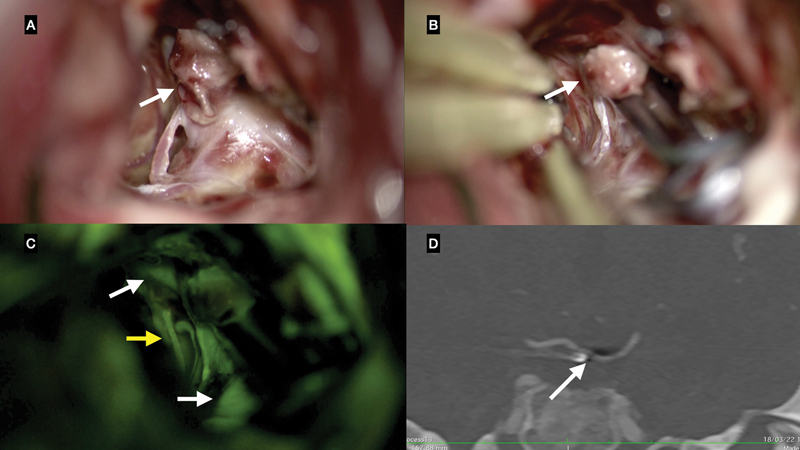

Results: FL-VA showed complete occlusion in 57 out of 61 aneurysms (93.4%), with 10 cases of discordance identified in postoperative CTA. One patient showed a neck remnant in FL-VA, but CTA revealed a residual aneurysm. Another patient displayed neck remnant and stenosis in branching vessels on CTA, not identified by FL-VA. Additionally, five aneurysms had neck remnants, and three had stenosis in branching vessels, detected in CTA but missed in FL-VA. Statistical analysis did not reveal significant associations between discordance and studied factors.